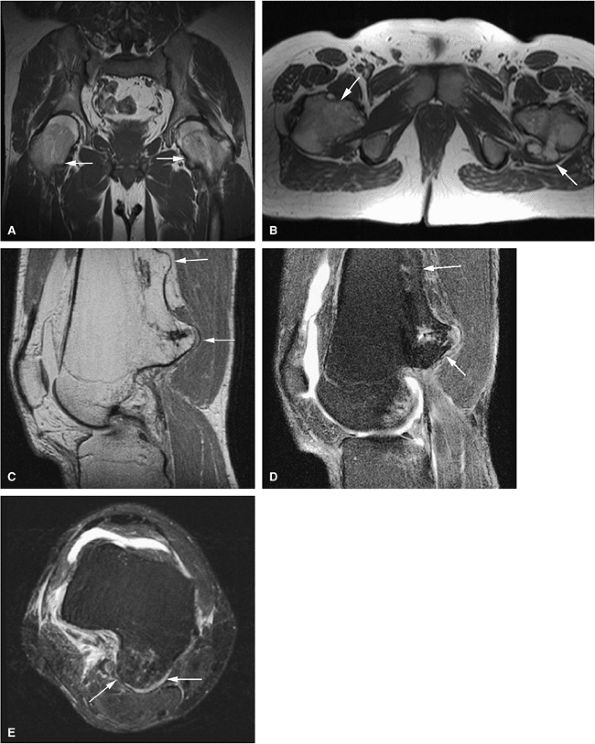

FIGURE 14-31 ● Undertubulation of the hips and knees in a patient with multiple hereditary exostoses. Exostoses (arrows) are seen on coronal (A) and axial (B) T1-weighted images of the hip. Sagittal proton density (C) and sagittal (D) and axial (E) fat-suppressed T2-weighted fast spin-echo images of the knee also demonstrate exostoses (arrows).